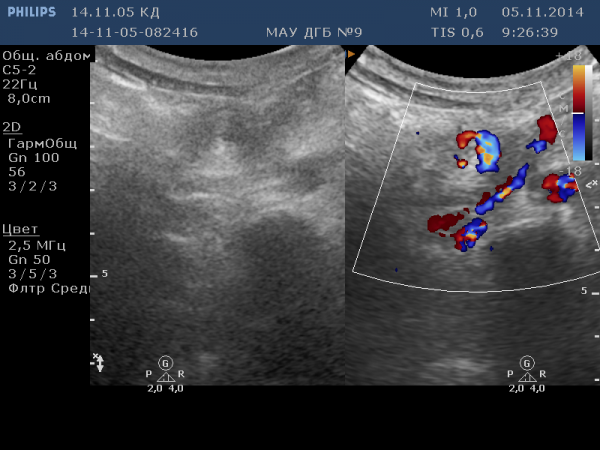

Пациент 5 лет, беспокоят приступообразные боли в животе, не купирующиеся спазмолитиками и рвота, которые повторяются уже несколько лет, по нескольку раз в год. Диагноз чётко поставить нигде не могут. За весь период делали рентгенологическое исследование, пациент не раз лежал в гастроэнтерологическом отделении и хирургии. И вот, вновь поступает в приёмное отделение с аналогичной острой клиникой (температуры нет, общие анализы крови и мочи нормальные, живот мягкий, болезненный).

Пояснение: на видео и фото обзор ведётся мезогастральной и частично - эпигастральной областей. Ваше мнение, коллеги?

Сначала, я как и вы был в замешательстве, покане включил ЦДК ... !lh!

То, что я вам представил в виде инвагината-это перекрученный корень брыжейки ( про Ледда я тоже подумал, но не был до конца уверен, ведь для Ледда данных УЗИ может оказаться недостаточно). Учитывая выраженную клинику, хирурги взяли пациента на операцию. В итоге -оказался "изолированный заворот брыжейки кишки" (на Ледда -структурных изменний оказалось мало)

Моё заключение : "объёмное образование в мезогастральной области.Дилатация и спиралевидный перекрут брыжеечных вен".